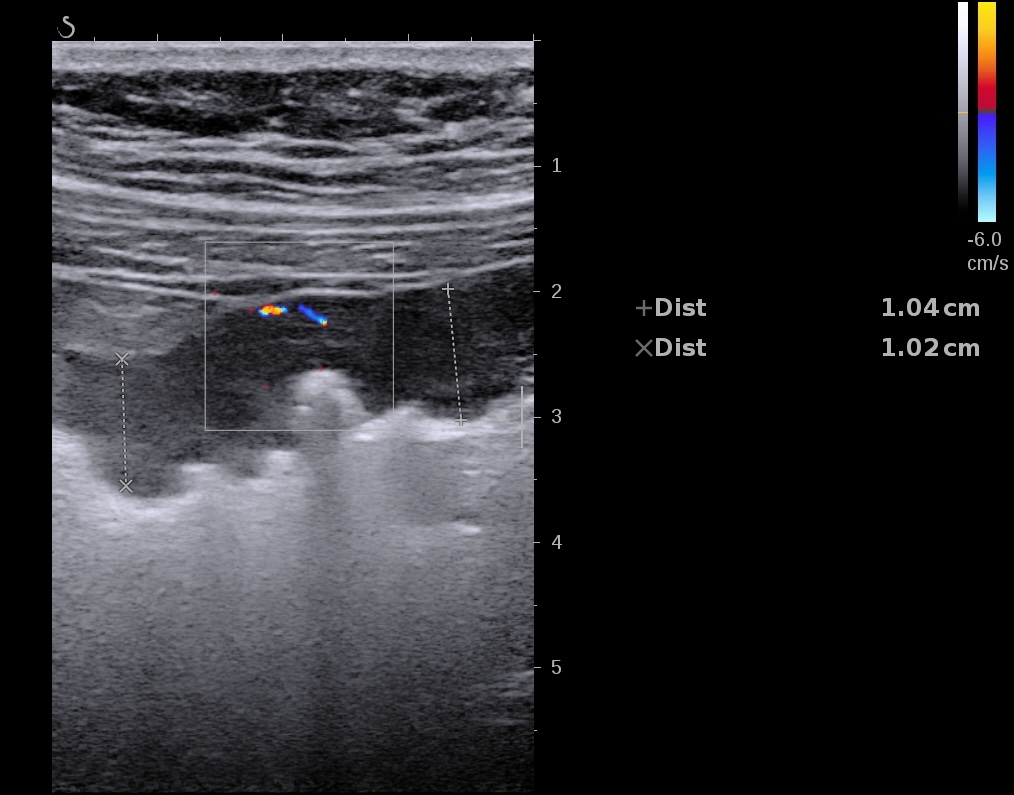

Epaississement considérable par endroit (10 ou 11 mm), disparition totale de la structure en couches, déformation de la surface avec ulcérations, déformation des contours, infiltration de la graisse, hyperactivité Doppler

Le Score de Milan (MUC) est à 17.4

Echographie: pancolite jusqu’à l’angle droit, Paroi 7 mm perte de la stratification, doppler positif.

Epaississement entre 4.5 et 7 mm selon les segment, la structure en couche disparait totalement par endroit, à d’autre elle est partiellement conservée. Activité doppler intense de la paroi

Le Score de Milan (MUC) est à (1,4 x7+2) = 11,8